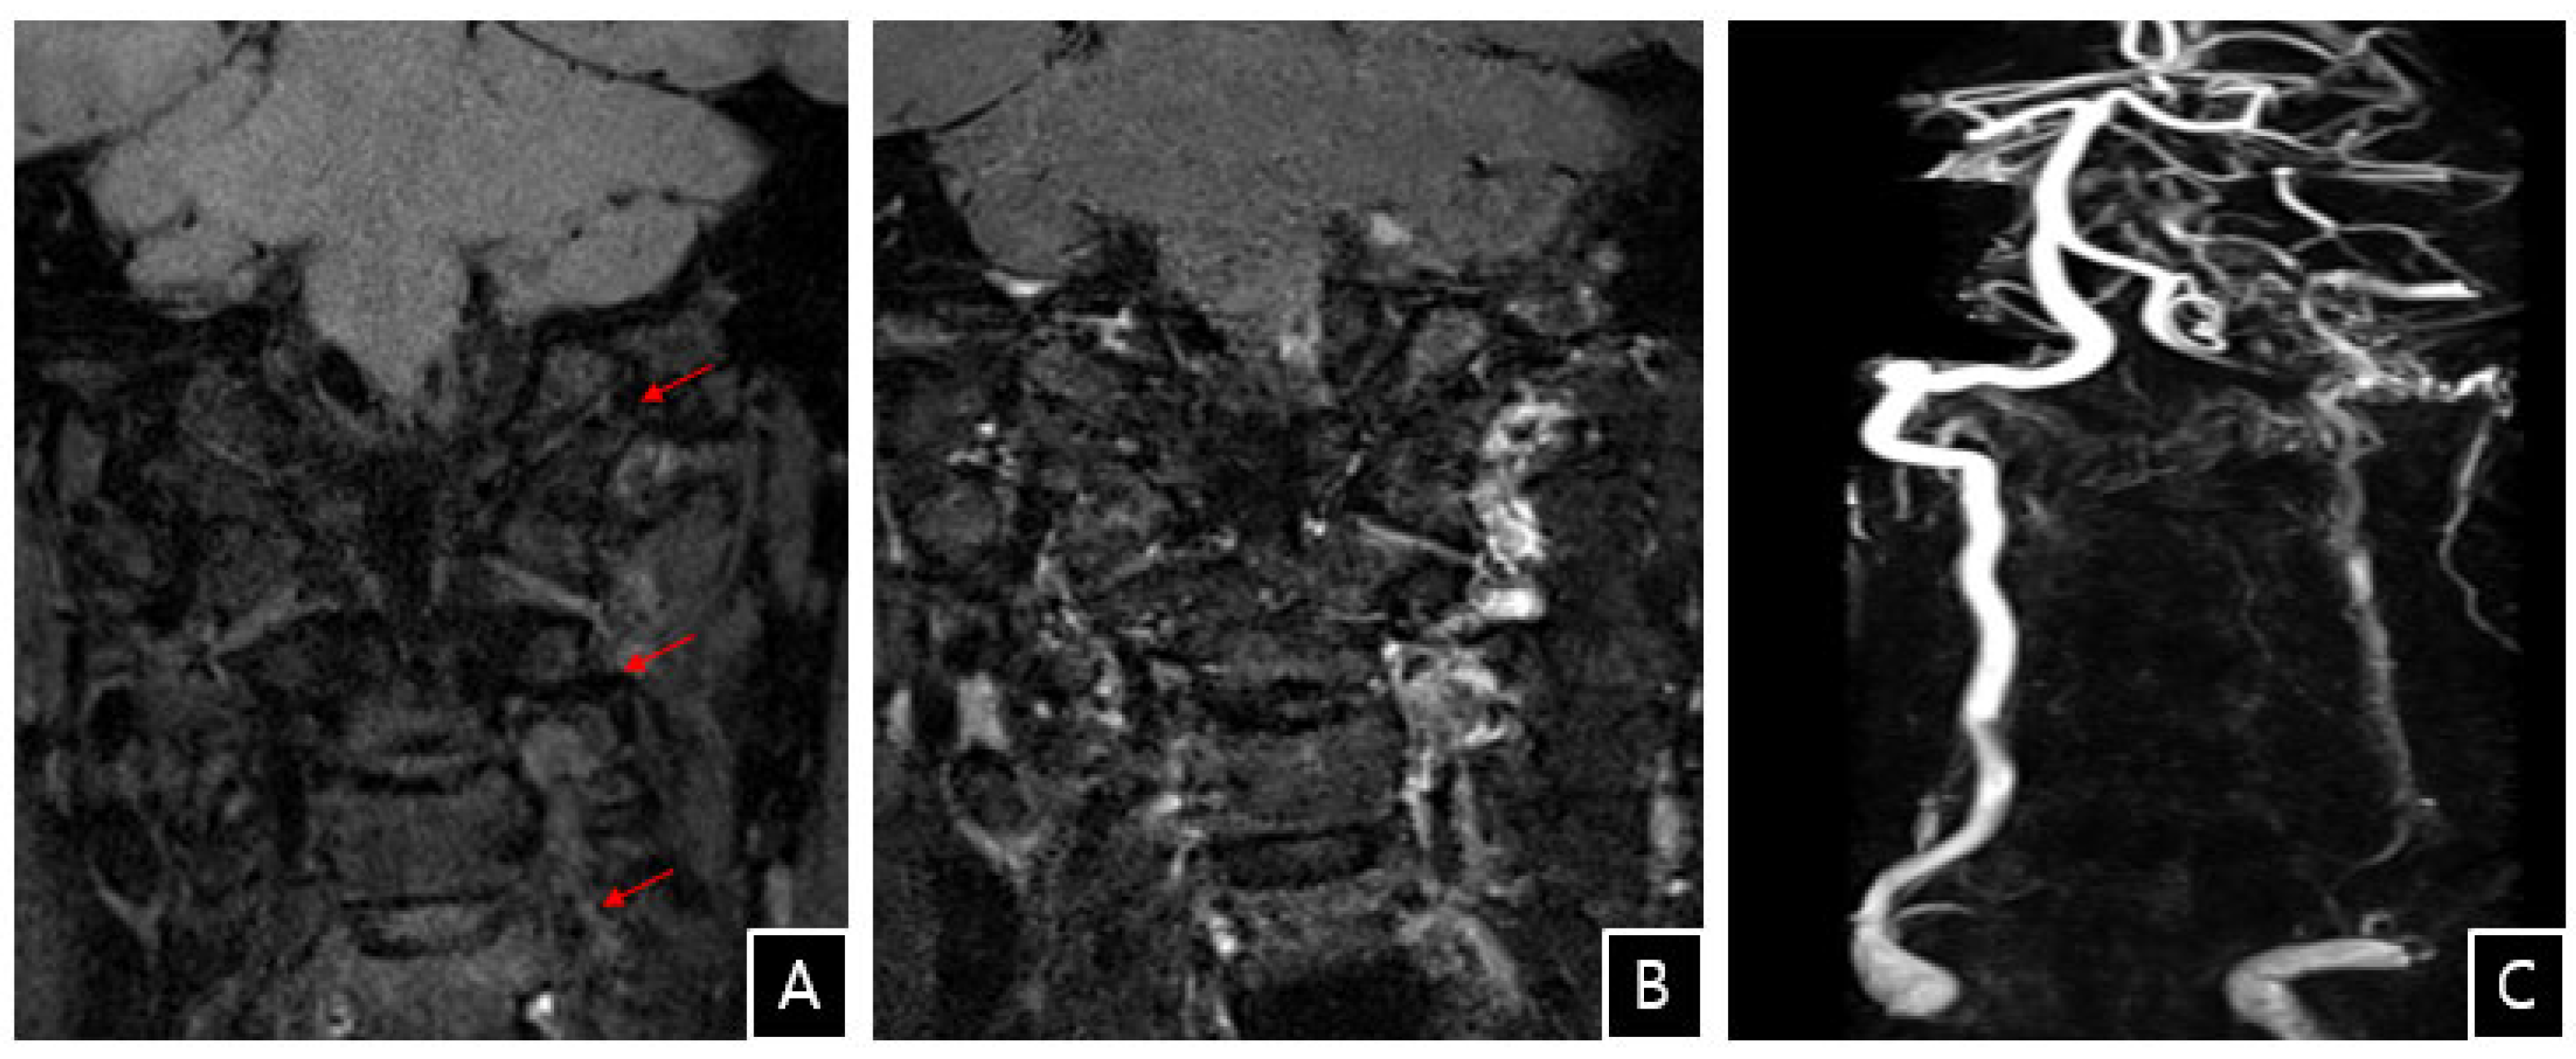

Vertebral artery dissection (VAD) is a rare vascular cause of acute stroke. Although VAD may be classified as spontaneous or traumatic, it is increasingly recognized that trivial mechanical stress typically precipitates this potentially dangerous condition. Herein, we report a rare case of VAD and acute stroke following anterior cervical decompression and artificial disc replacement (ADR). To our knowledge, there have been no other cases of acute vertebrobasilar stroke caused by VAD following anterior cervical decompression and ADR. This case highlights that, although rare, acute vertebrobasilar stroke may occur after the anterior cervical approach.